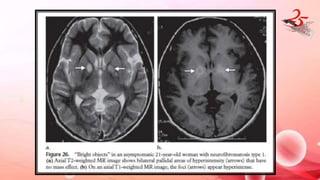

NEUROFIBROMATOSIS TYPE I

• MC neurocutaneous syndrome

• CLINICAL FEATURES : café-au-lait spots, axillary freckling, Lisch

nodules, neurofibromas, plexiform neurofibromas, optic glioma,

bone dysplasias, or pseudoarthrosis.

IMAGING FINDINGS: Focal T2 hyperintense and TI hypointense in

GP > brainstem and cerebellum

• NO mass effect

• No surrounding edema

• No CE

• MRS : high NAA-Ch , Naa-Cr and Cr- Cho ratios